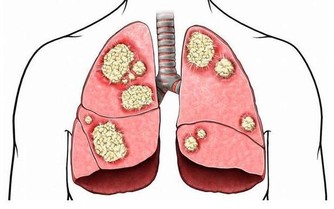

原來Josef是因為最近出現背痛、呼吸不順的症狀,才趕快赴往醫院檢查,起初他以為是肥胖因素導致身體出狀況,不過到院檢查後卻發現是肚子裡長著一顆腫瘤,大到已經擠壓到附近的器官:腎臟、肝臟與肺部,為求保命在醫生的建議下立即動手術移除腫瘤。

最後這場手術歷經六小時才成功切除腫瘤,待醫生一秤之下才知道這顆腫瘤重達27公斤。